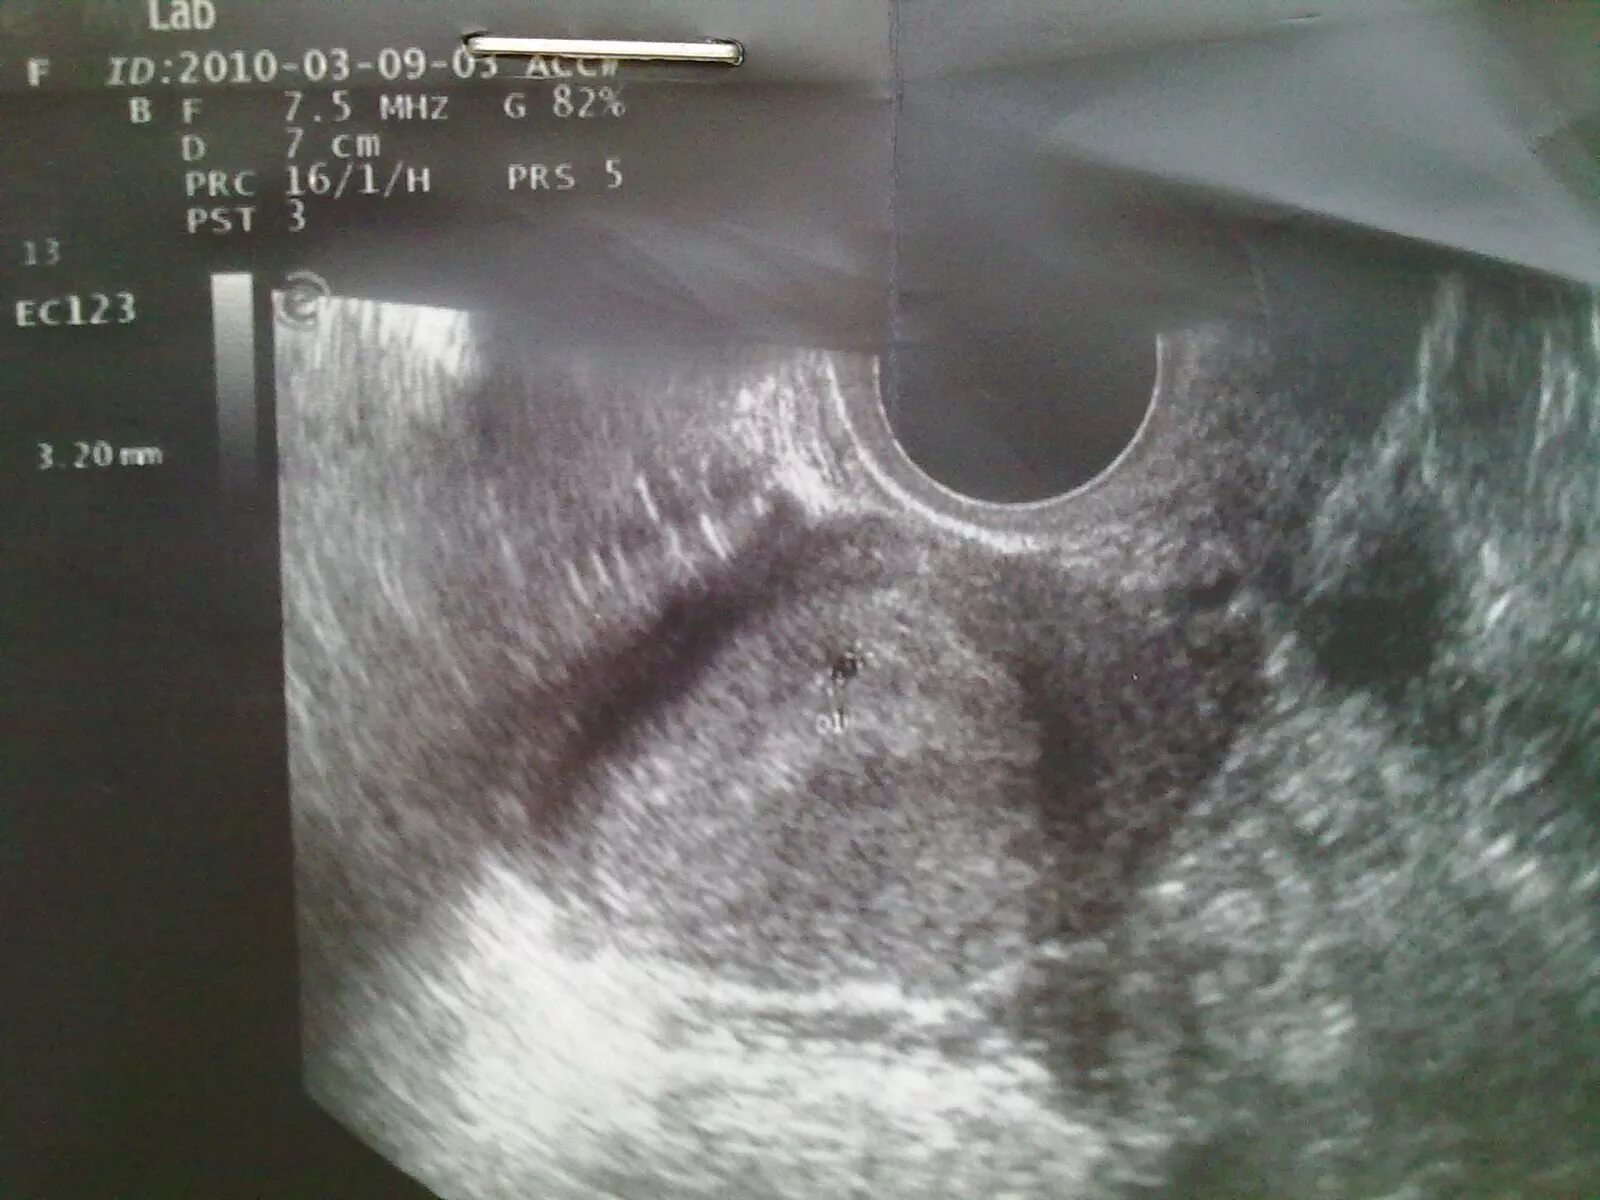

Плодное яйцо 3 мм